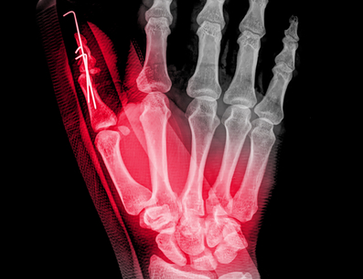

Hand & Upper Extremity

Trauma